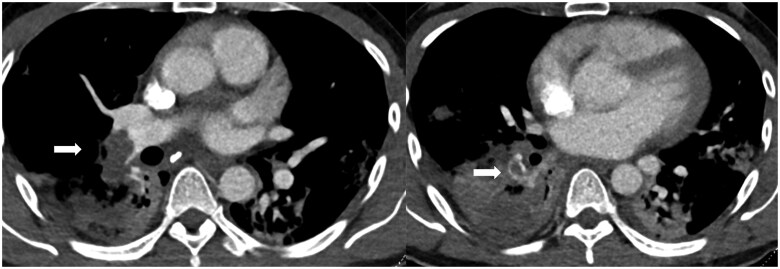

急性肺栓塞可以表现为一系列生理状态,从偶然发现到危及生命的右心衰。我们讨论了成像在准确和快速诊断中所起的关键作用。此外,影像学特征是评估表现严重程度的核心,允许适当的风险分层和护理升级。各种成像方式用于慢性血栓栓塞性肺动脉高压的管理的相对优势也进行了讨论。

Acute pulmonary emboli can manifest as a spectrum of physiological status ranging from an incidental finding to life threatening right heart failure. We discuss the crucial role imaging plays in the accurate and rapid diagnosis. In addition, imaging features are central in assessing the severity of the presentation allowing for appropriate risk stratification and escalation of care. The relative strengths of the various imaging modalities used in the management of chronic thromboembolic pulmonary hypertension are also discussed.